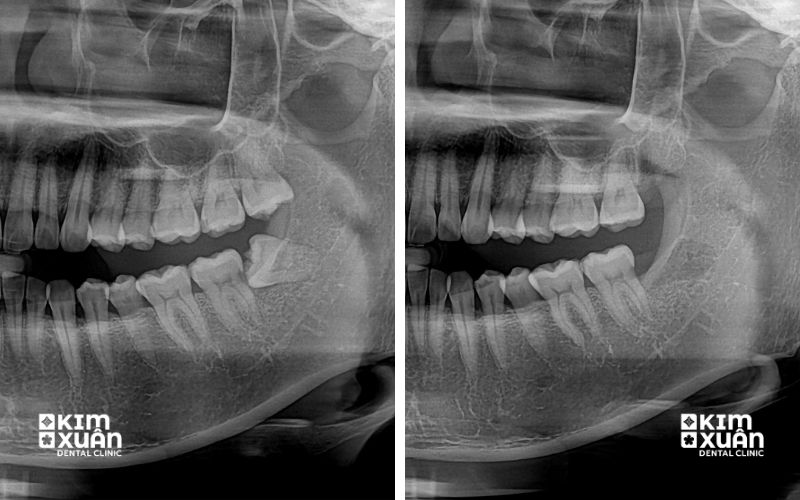

Thăm khám nha khoa định kỳ, kết hợp chụp phim X-quang để theo dõi chính xác hướng mọc và tình trạng răng khôn